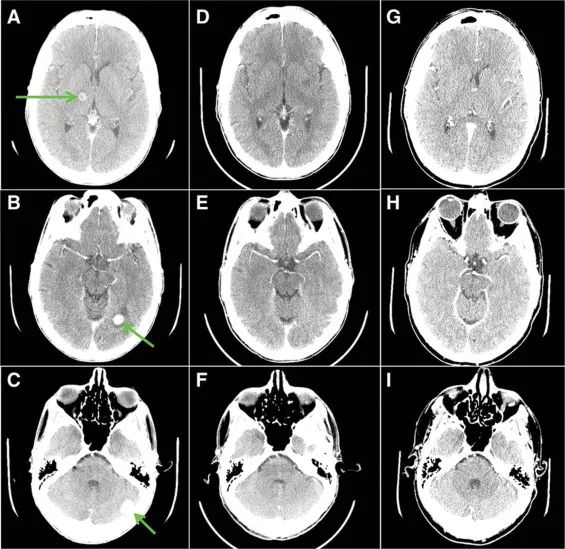

R先生确诊时非常年轻,仅仅26岁。检查结果证实他所患为ROS1阳性的肺腺癌,Ⅳc期(TxN2M1c),已经有骨等多个部位的广泛转移或浸润。

他一线使用了克唑替尼治疗,以及针对骨转移的放疗等处理措施。3个月后复查的MRI显示,R先生的脑内出现了17个转移病灶!

克唑替尼本身的入脑活性并不理想,R先生只能继续接受脑部的放疗(射波刀)来消除脑部病灶,并继续使用克唑替尼控制身体其他部位的肿瘤。整体来说疗效不错,病灶有比较明显的缩小。

然而,在克唑替尼治疗14个月后,R先生脑部的MRI扫描再次提示,出现了超过40个新的微转移病灶!

但是此时R先生的进展部位只有脑,身体其他部位的病灶仍然与之前相比有缩小,因此他换用了与克唑替尼同为第一代ROS1抑制剂、但治疗脑转移病灶效果更好的恩曲替尼。

恩曲替尼治疗持续了6个月,MRI检测显示R先生颅内的病灶增大且出现了新的病灶,但是身体其它部位的病灶仍有控制效果。经过研判,R先生接受了同情用药,开始使用当时尚未上市的劳拉替尼。

劳拉替尼属于第三代ALK抑制剂,由于对克唑替尼耐药后的患者也有不错的疗效,而同时归属于第二代ROS1抑制剂的范畴。治疗仅2个月之后,R先生脑内的病灶开始出现了缓解!